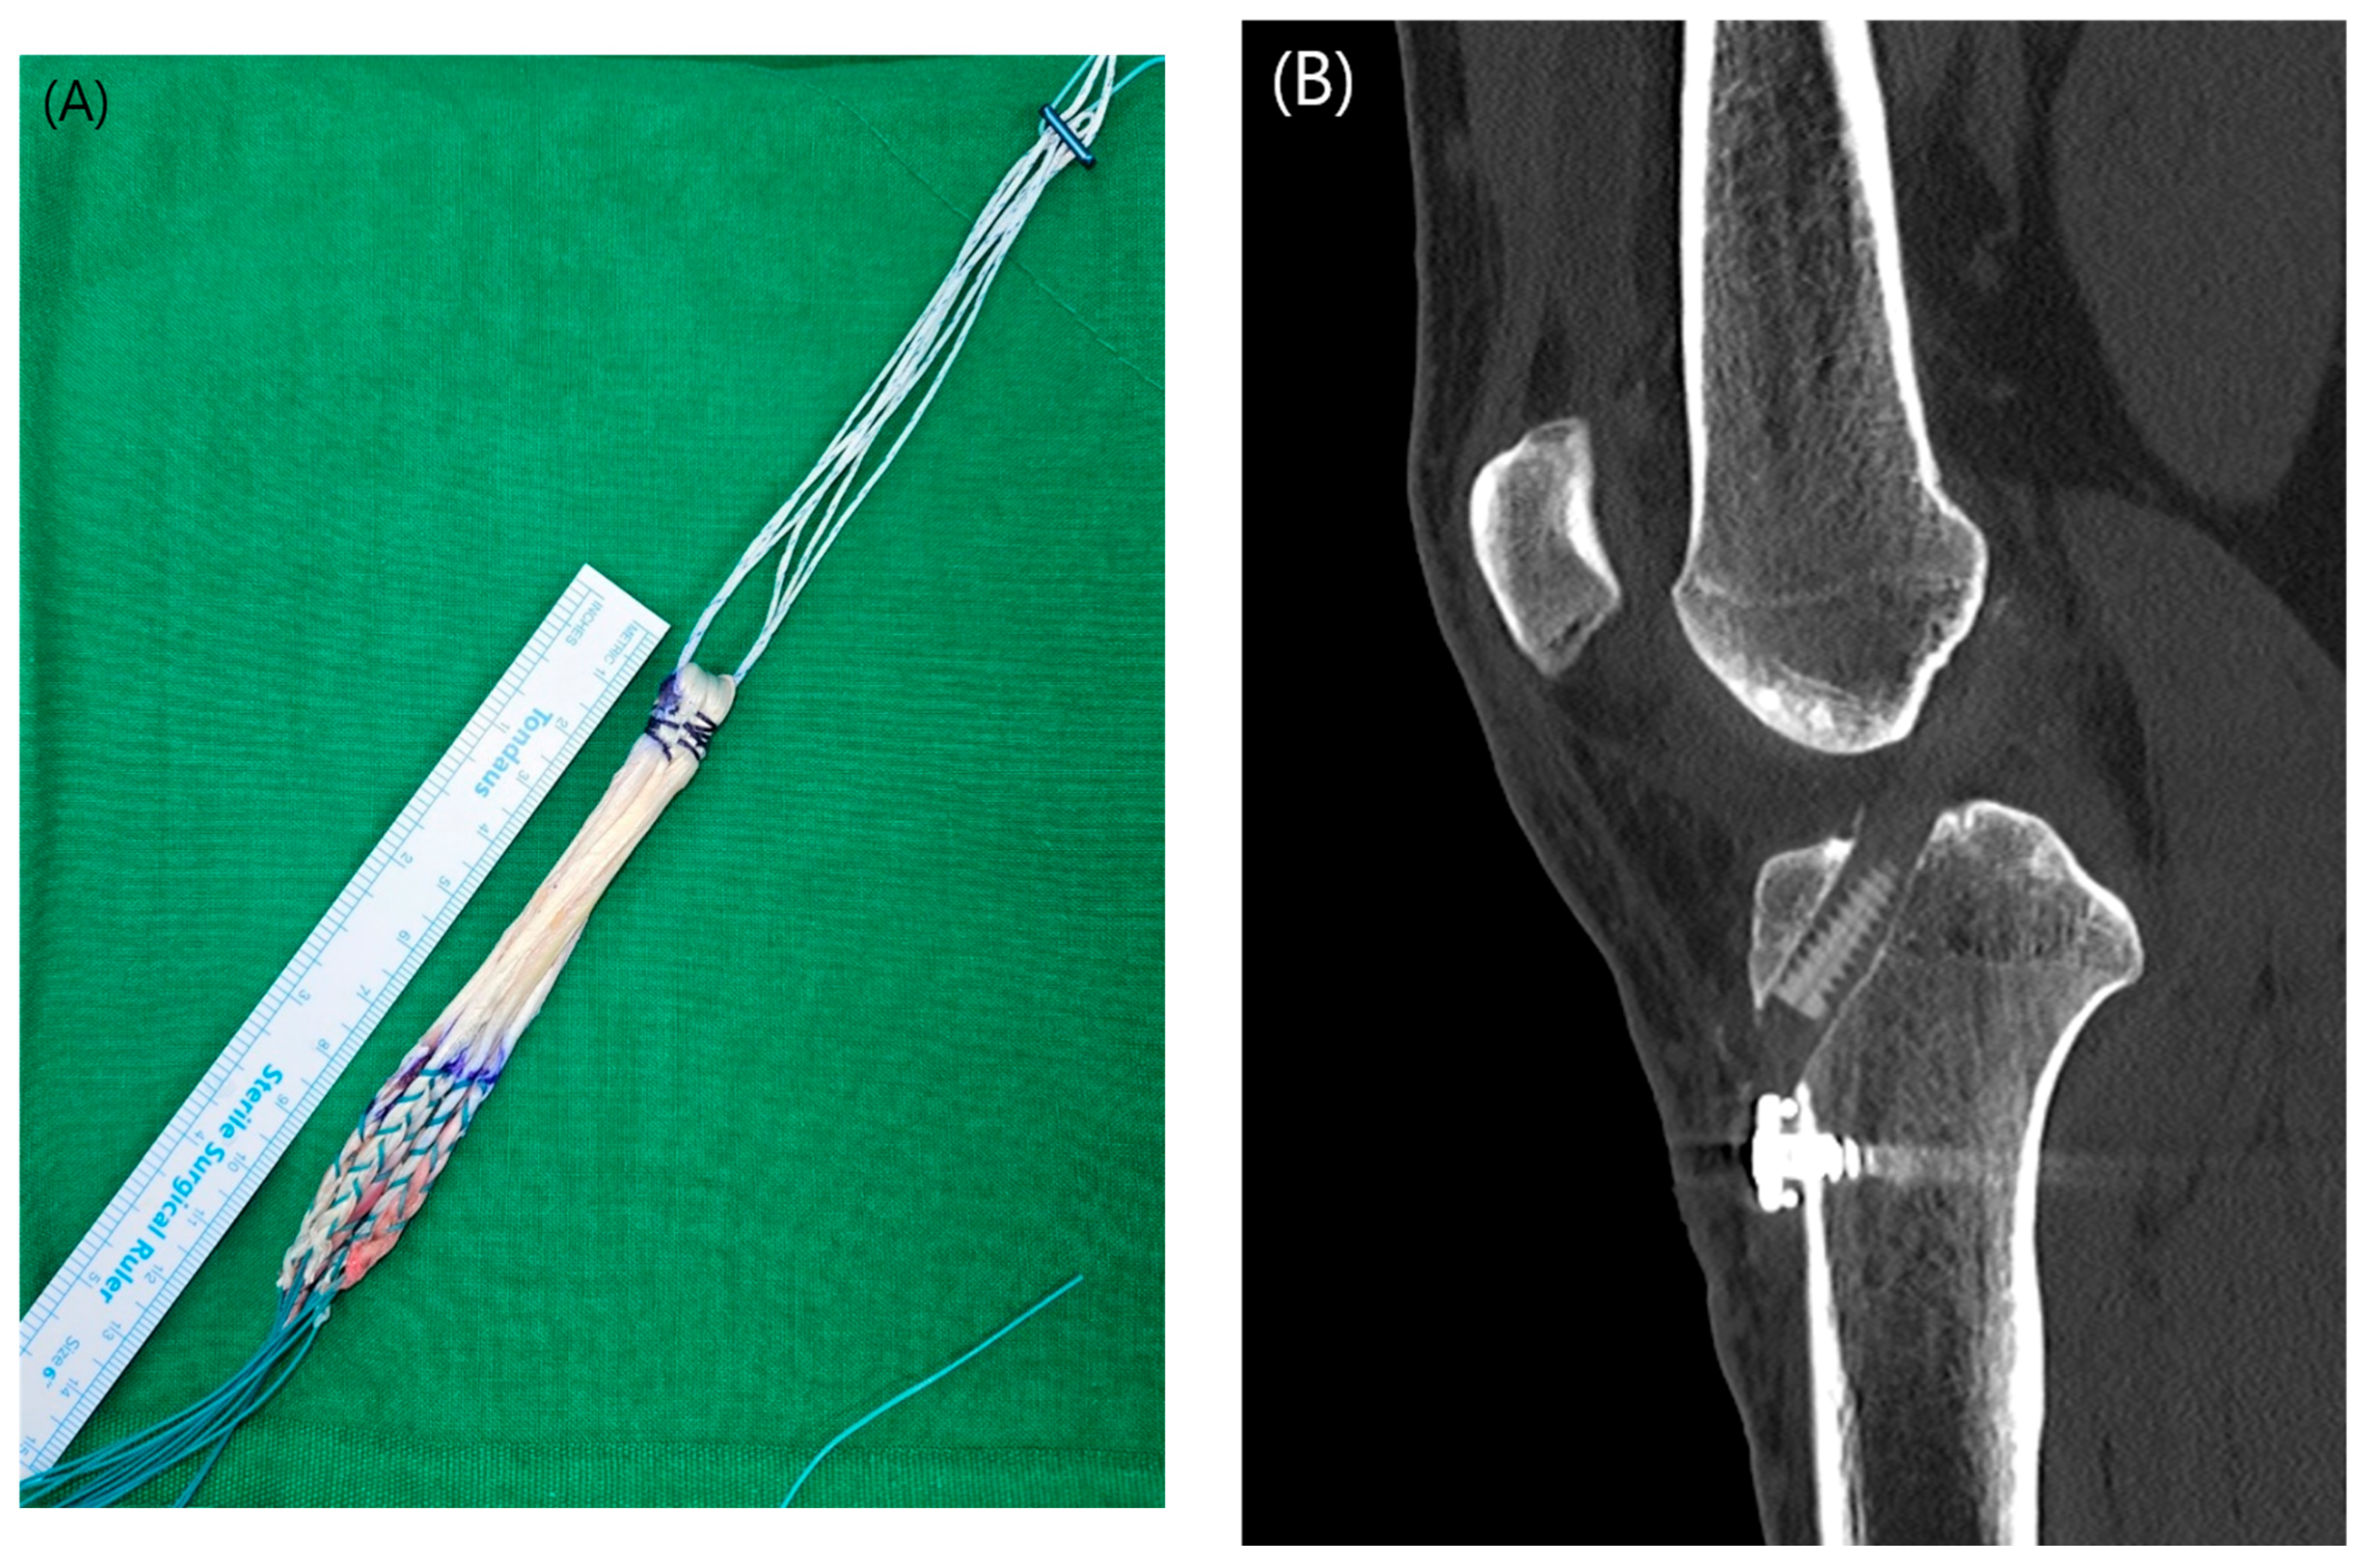

In the standard full tibia group (FT-4 group), a full-length tibial tunnel was drilled using the conventional technique, starting from the anteromedial cortex. The graft was prepared using a double-folded 4-strand hamstring autograft, utilizing both the semitendinosus and gracilis tendons (Figure 2(A)).

Fixation in the FT-4 group was achieved using an adjustable suspensory device on the femoral side. On the tibial side, an interference screw was used for primary fixation, with additional fixation performed using a screw and spike washer (Figure 2(B)).

Figure 2. (A) Completed configuration of a four-strand hamstring autograft. (B) Sagittal computed tomography scan depicting the morphology of the full-length tibial tunnel after standard ACL reconstruction.